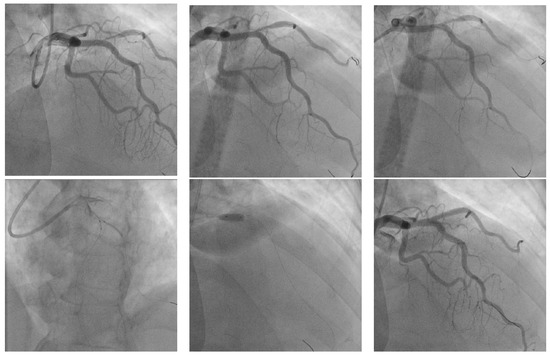

T and Small Protrusion (TAP) Technique in Bifurcations: Coronary Artery Disease in Acute Myocardial Infarction Patients after COVID-19 Pneumonia

Ischemic coronary artery disease in all its forms remains the main cause of death worldwide. Coronary artery bifurcation lesions are a challenge because of their complexity and possible complications. The goal of treating bifurcation lesions is the optimal revascularization of the main vessel without compromising the side branch. Although the study of bifurcation stenting aims to keep the side branch viable, the outcomes regarding major acute cardiovascular events and survivability are related to the optimal treatment of the main vessel. There are many trials that have tried to evaluate the best technique to use with respect to bifurcation lesions, and early studies support provisional stenting as the election treatment. More recent trials highlighted the superior outcomes of the double kissing crush technique used on unprotected distal left main bifurcation lesions. In patients with acute myocardial infarction, two-stent techniques were avoided because of the prolonged procedural time in unstable patients, with high risks of complications. We present the case of a 53-year-old woman with multiple cardiovascular risk factors (dyslipidemia, hypertension, active cancer, post-COVID-19 state) and acute antero-lateral myocardial infarction who underwent primary coronary intervention with the use of the TAP technique for stenting the bifurcation culprit coronary lesion (left anterior descendent artery and first diagonal artery). Full article

Show Figures

Graphical abstract